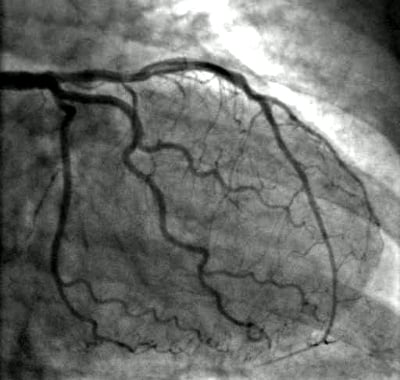

PCI owes its precision, safety and effectiveness to X-ray fluoroscopy imaging. The amount of radiation dose used during procedures is generally much greater than that used for a typical X-ray image, such as a chest X-ray. But because a chest X-ray is usually a screening test and a PCI is a lifesaving procedure, from the clinical perspective, the risk of not performing the PCI is much greater than the predicted radiation risk associated with the procedure.

• Indicators of higher radiation dose included male gender higher body mass index (BMI); more complex disease, such as multiple diseased vessels or complex anatomy and lesions in the vessels; and previous history of coronary artery bypass graft (CABG) surgery.